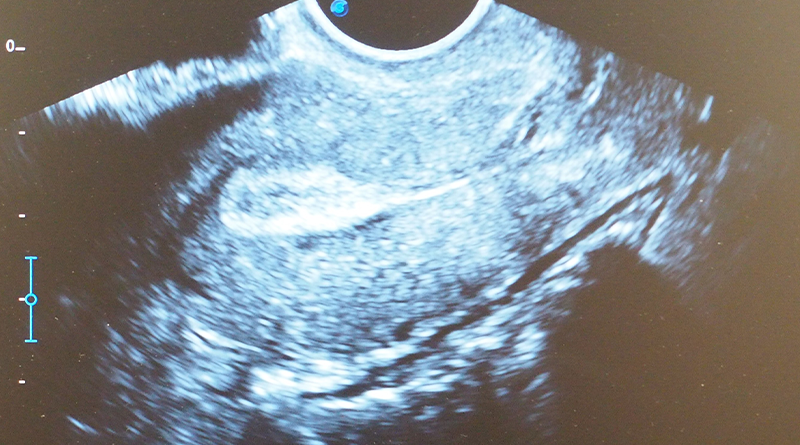

อัลตราซาวด์ทางนรีเวช หรือ "อัลตราซาวด์มดลูกและรังไข่" เป็นการตรวจภายในที่ใช้คลื่นเสียงความถี่สูงเพื่อตรวจดูอวัยวะภายในสตรี ได้แก่ มดลูก ปีกมดลูก รังไข่ และเยื่อบุโพรงมดลูก โดยไม่ต้องผ่าตัด ไม่เจ็บ และไม่ใช้รังสี จึงสามารถใช้ตรวจหาความผิดปกติได้อย่างปลอดภัยและแม่นยำ

ที่ VIVV Clinic เราใช้เครื่องอัลตราซาวด์คุณภาพสูง พร้อมการแปลผลโดยแพทย์เฉพาะทางสูตินรีเวช เพื่อให้คุณมั่นใจในผลการตรวจ